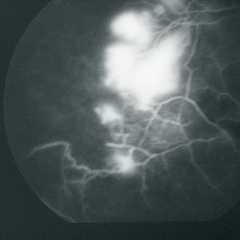

Posterior pole of the right eye of a 23-year-old Vietnamese female with Eales disease; V.A.= 20/40.

Imaging device: Topcon VT-50

Condition/keywords: Eales disease